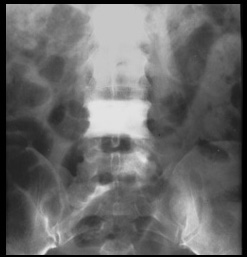

Subdiaphragmatic lymphadenopathy, both retroperitoneal and intraperitoneal, has been reported in up to one-half of these patients. The lymph nodes are usually discrete and mildly enlarged, but marked lymphadenopathy and large conglomerate nodes do occur.

There are multiple enlarged paraaortic, paracaval, and porta hepatis lymph nodes (arrows).

There are multiple calcifications of the kidneys (nephrocalcinosis) as a result of hypercalcemia. Note enlarged retroperitoneal lymph nodes (arrows) which is a common finding in sarcoidosis.